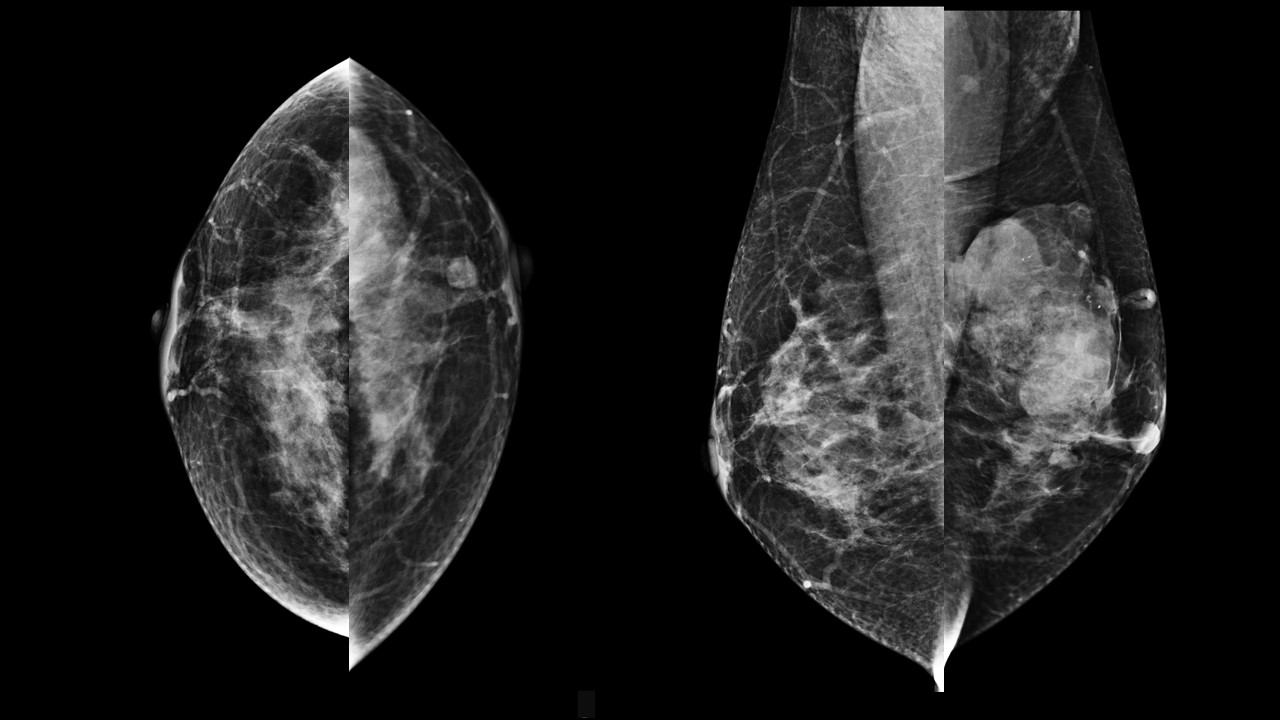

A 48-year old woman presented with painless palpable right breast lump...

Read More